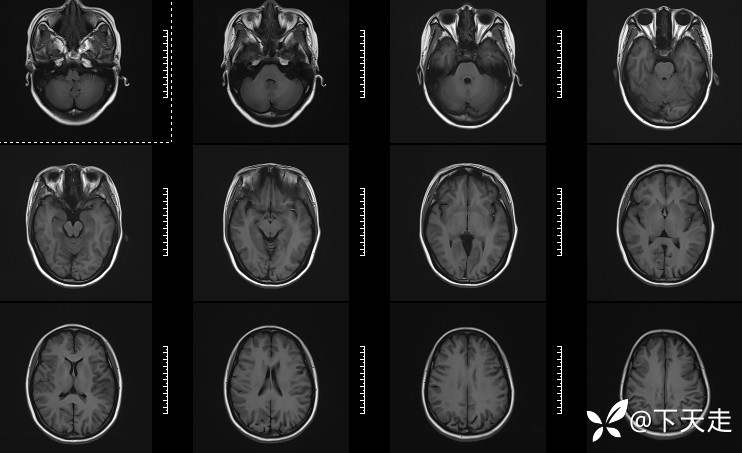

青鹊词 推荐青年女性,37岁,因不能言语就诊于耳鼻喉科,耳鼻喉科医生诊疗后建议神经内科就诊。

查体:神清,完全性运动性失语,四肢肌张力正常,肌力5级。

相关检验检查资料如下